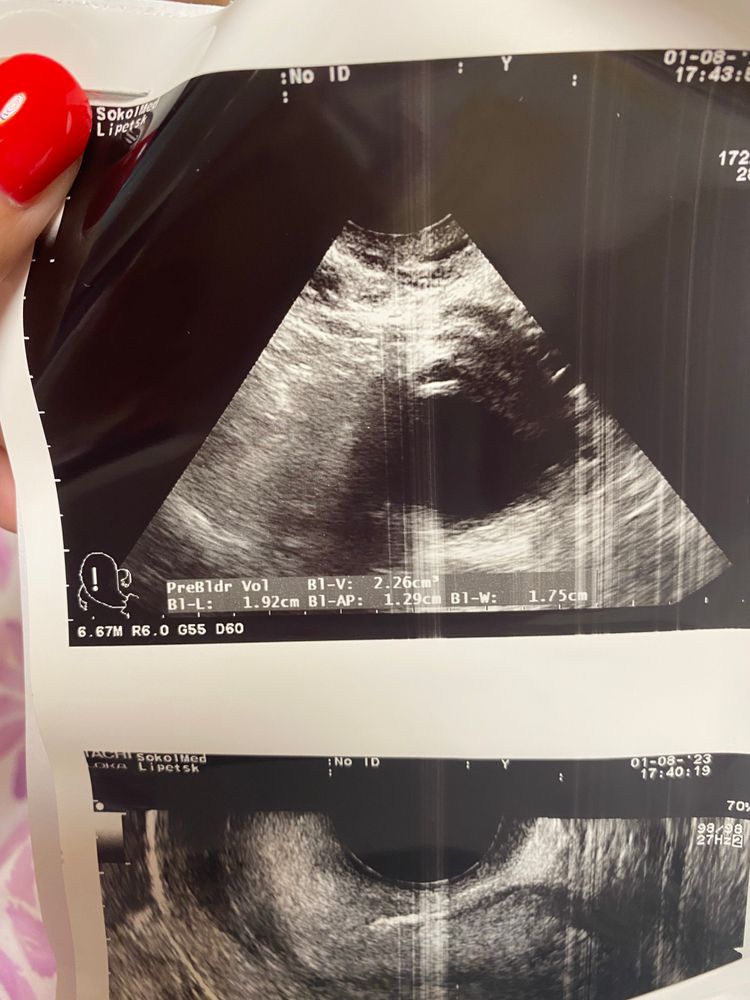

Позавчера было узи у моего гинеколога, эндометрий 9.7 доминантный фолликул 20 мм. После чего был укол хгч 10000. Позавчера! Пришла сегодня на узи ( тот же самый аппарат) другой узист (моя в отпуск ушла) она мне сказала, что ДФ=18 и эндометрий всего 6! Я могу предположить, что фолликул сдулся, но куда делся эндометрий? И кто-то понимает по картинкам, может, это ЖТ? А не фолликул? верхнее фото сегодня-нижнее позавчера

Мне кажется это жт.Без четкой контуры . Фолликул он та круглый аккуратный .Я сравниваю по своему узи просто )тоже была на стимуляции

Не верхнем подозреваю все таки формирование желтого тела!